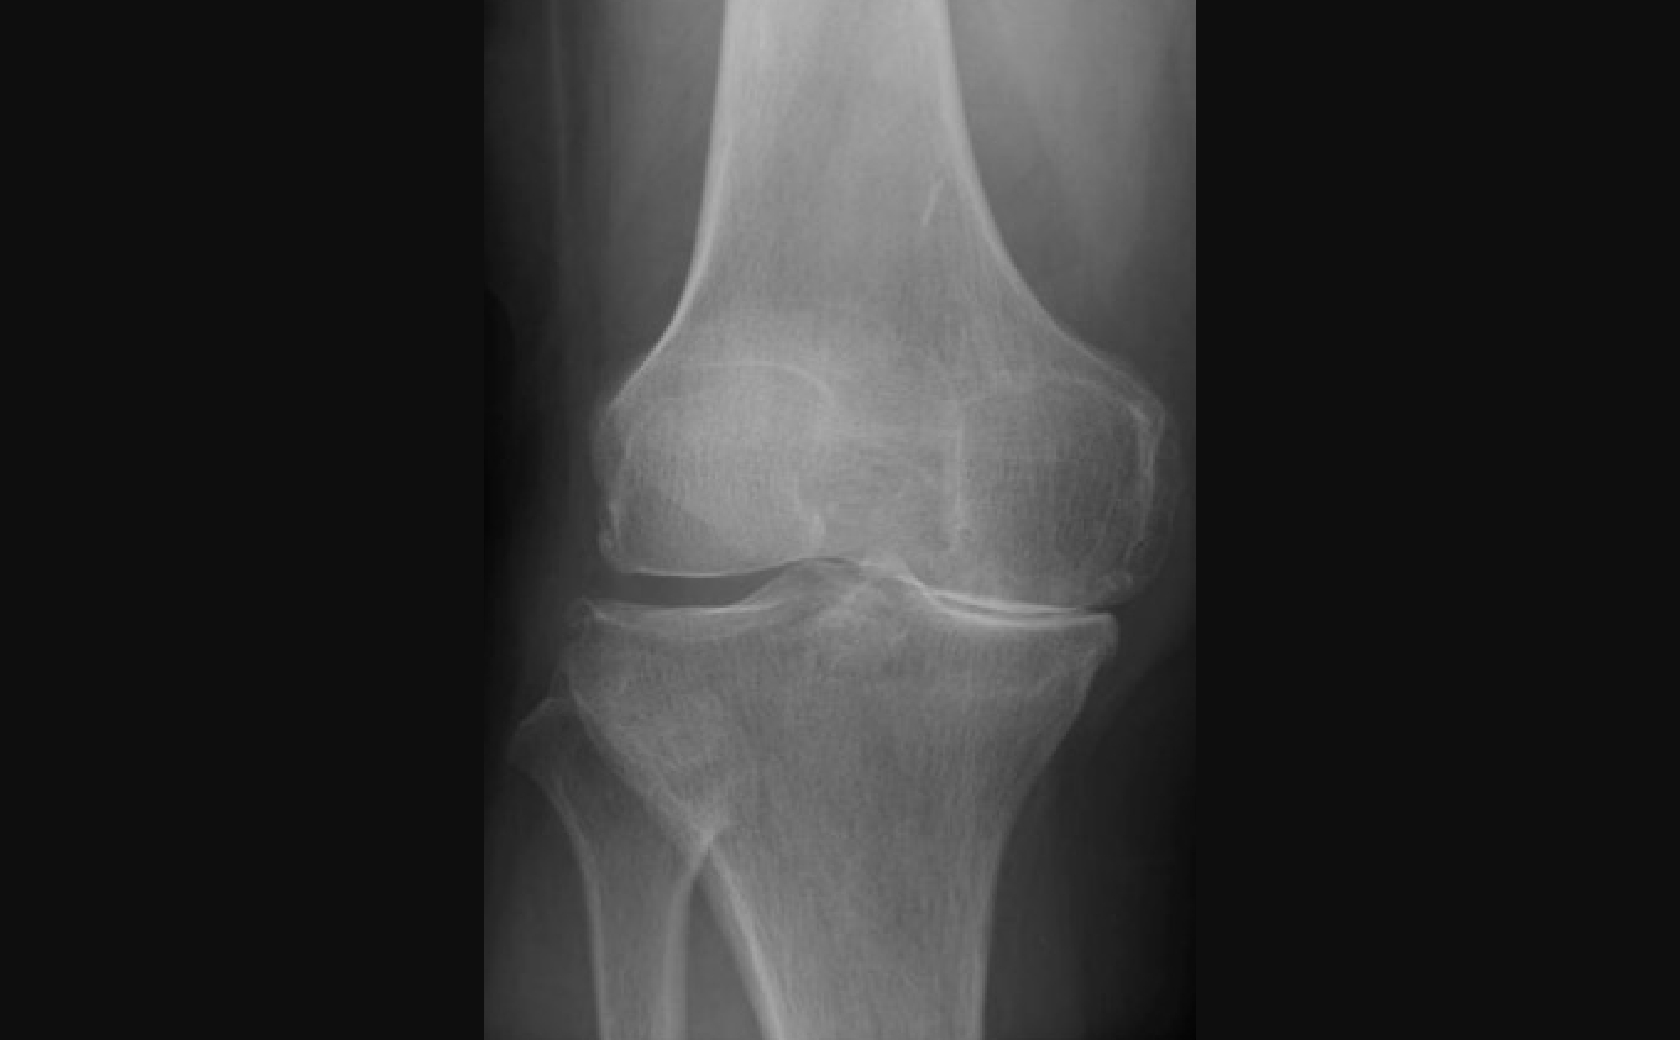

手術前後レントゲン画像

全人工膝関節置換術

術前